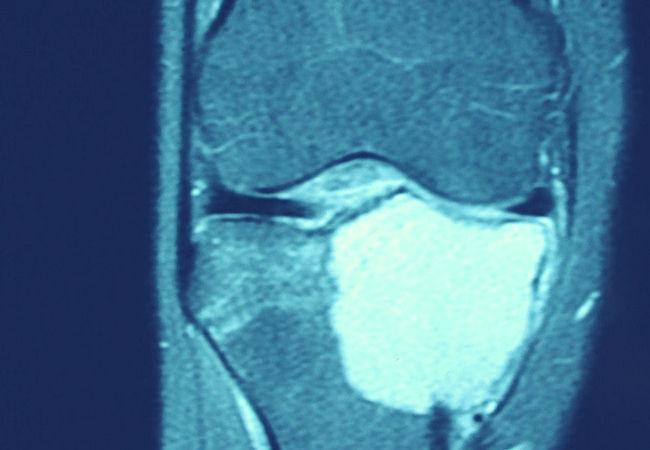

O diagnóstico é feito pelo médico através da história, exame físico, exames de imagem e anatomopatológico e sua correlação com os diagnósticos diferenciais. O aspecto radiográfico é de uma lesão lítica, redonda ou oval, localizada. A cortical óssea pode estar insuflada e o osso subcondral destruído dando a impressão da lesão se comunicar com a articulação. A Tomografia Computadorizada e Ressonância Magnética são úteis para avaliar com maior precisão a localização e extensão da lesão na epífise, a presença de calcificações no interior e o comprometimento da placa de crescimento. No Anátomo Patológico aparece tecido celular relativamente indiferenciado, constituído por células redondas ou poligonais, semelhantes aos condroblastos, e por células gigantes multinucleares do tipo osteoclástico isoladas ou em grupos.